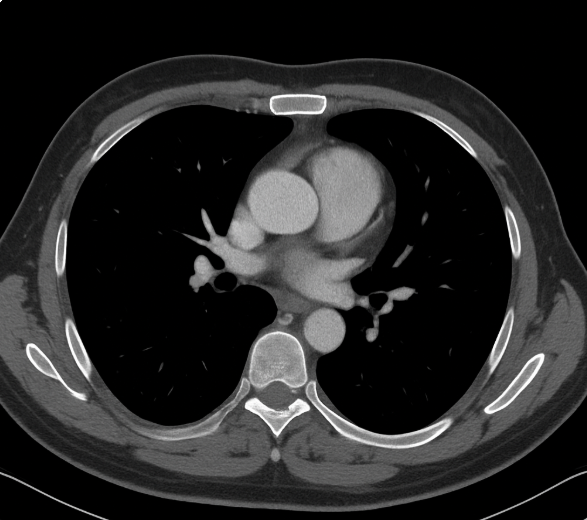

Computed tomography of the chest

No evidence of tumor activity in the lungs. Grade I cardiomegaly (Figure 3).

Computed tomography of the chest. No evidence of tumor activity in the lungs. Grade I cardiomegaly.